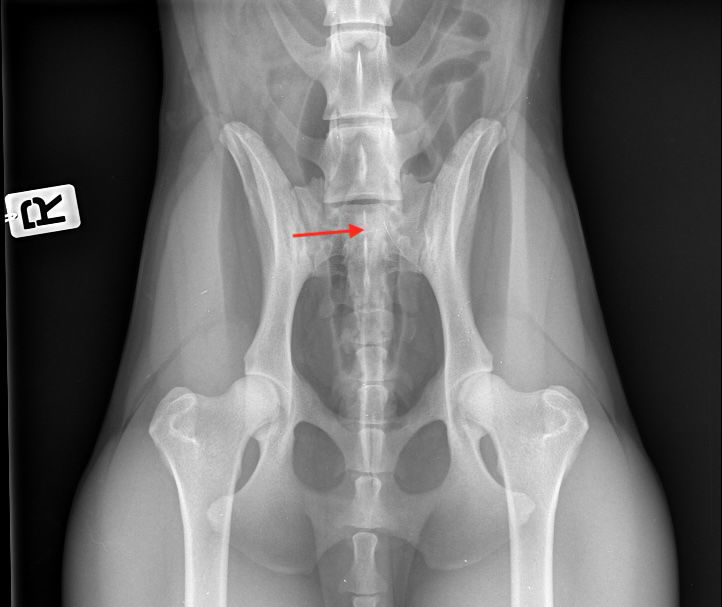

LTV1

Delt ´sacral crest´